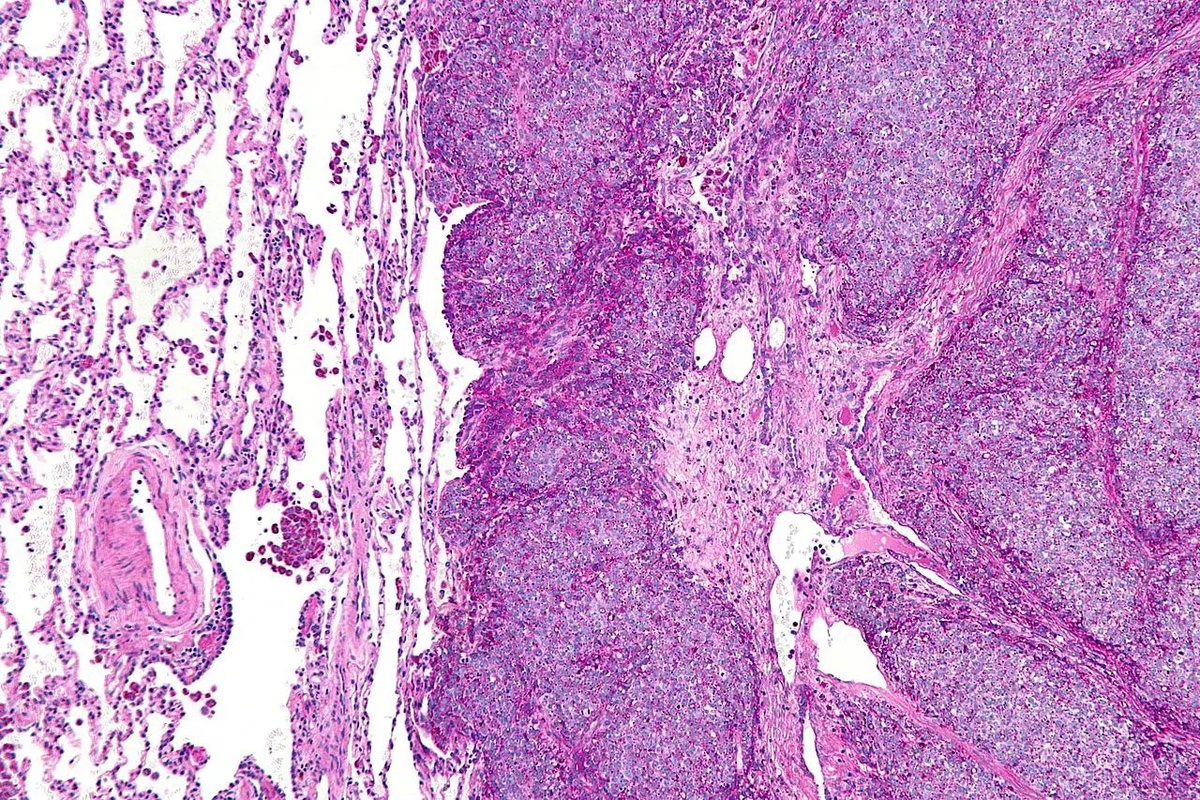

Институт биологии гена РАН и Сеченовский университет разработали новый метод лечения саркомы Юинга, используя микрочастицы на основе лактоферрина. Эти частицы доставляют ингибитор карбоангидразы II (OX72) непосредственно в опухоль, активируя ферроптоз (особую форму клеточной гибели). Метод показал эффективность против лекарственно-устойчивых форм саркомы Юинга.